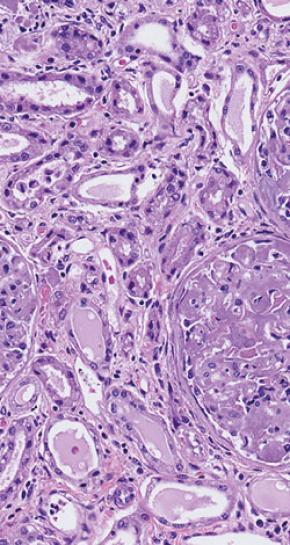

De fibrillen stapelen zich op in organen en weefsels zoals de nieren en het hart

Deze verkeerd gevouwen stukjes eiwit klitten weer samen tot zogenoemde fibrillen. De fibrillen kunnen moeilijk worden afgebroken en stapelen zich op in organen en weefsels, zoals de nieren, hart, lever, maagdarmkanaal en zenuwen.

De organen functioneren hierdoor slechter en er kunnen allerlei ziekteverschijnselen ontstaan. Dit ziektebeeld noemen we amyloïdose, ook wel een eiwitvouwaandoening of stapelingsziekte.